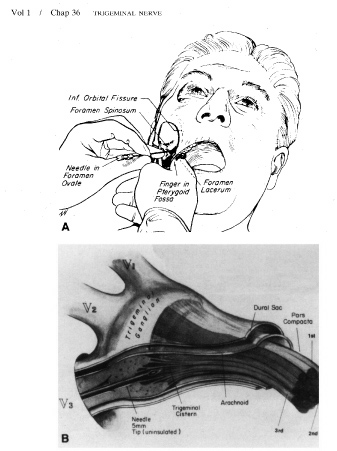

destruction of pain fibers. Part 1: Trigeminal neuralgia. J Neurosurg 39:143, 1974 85. Apfelbaum RI: A comparison of percutaneous radiofrequency trigeminal neurolysis and microvascular

decompression of the trigeminal nerve for the treatment of